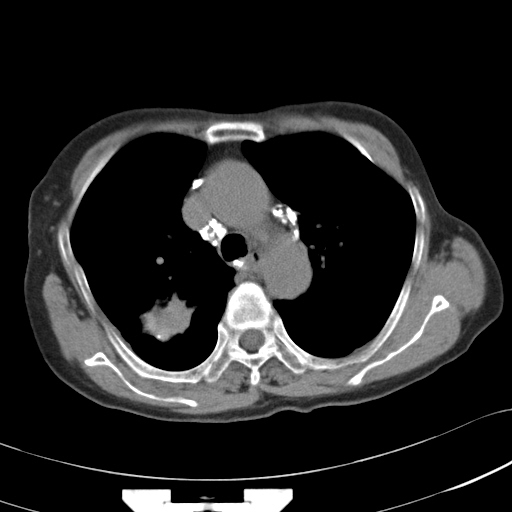

以下是引用hhcckk在2007-3-2 14:51:00的发言:[br]考虑结核球可能性大,依据[br]1病灶在下叶背段,结核的好发部位[br]2病灶内有大量的钙化,纵隔内有大量的淋巴结钙化[br]3重要的是半年前与现在相比无变化,假如是肿瘤的话不会这么‘善良’[br]4病灶周围卫星灶不明显,病灶有毛刺,胸膜凹陷,肿瘤不能完全排除,有条件的话最好做个活检

以下是引用liuyue在2007-3-2 17:15:00的发言:[br]1位置:右上叶后段[br]2性质:大分叶、粗长毛刺、条状斑片状钙化、纵隔多发淋巴结钙化,无强化,故考虑:肺结核灶(陈旧)